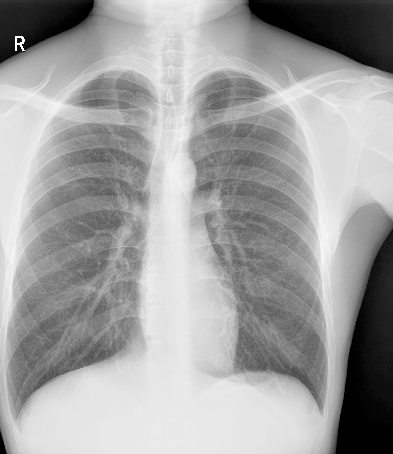

临床图像